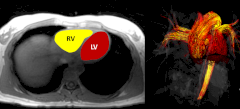

Исследователи из Висконсинского университета в Мадисоне сделали передовые 4D-снимки МРТ сердец 39 здоровых мужчин и женщин. И воочию убедились, что кровь циркулирует у участников по-разному.